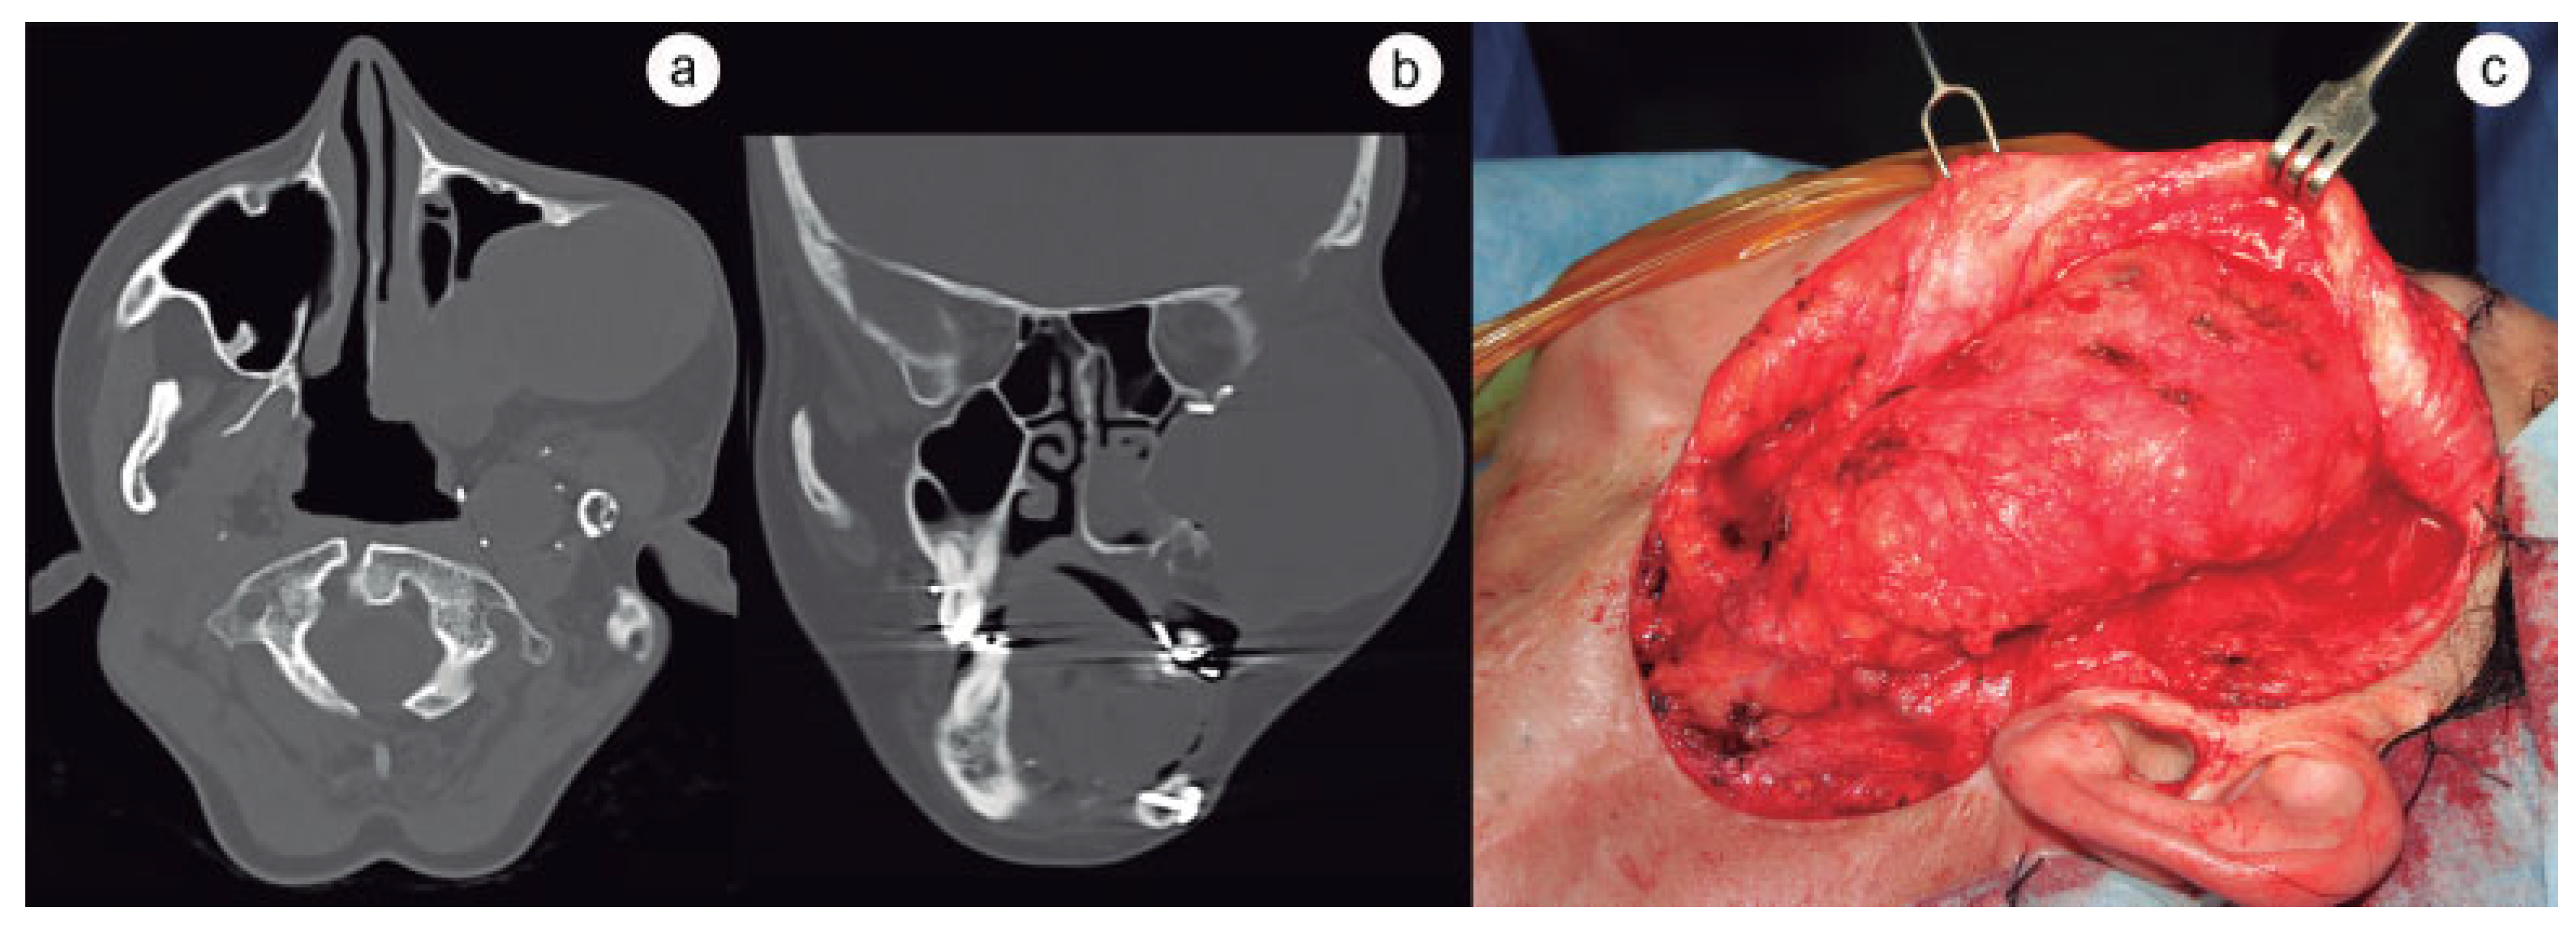

:Case History

Discussion